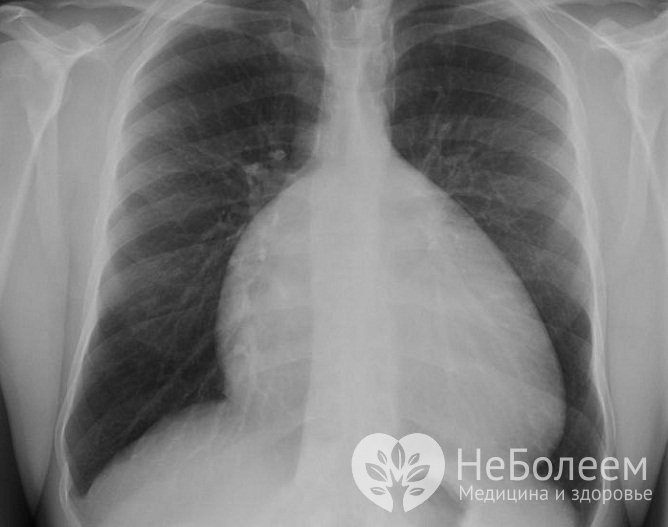

Рентгеновский снимок аномалии ЭбштейнаОсновным способом радикального устранения аномалии Эбштейна является хирургическое вмешательство, которое может осуществляться в один или несколько этапов.